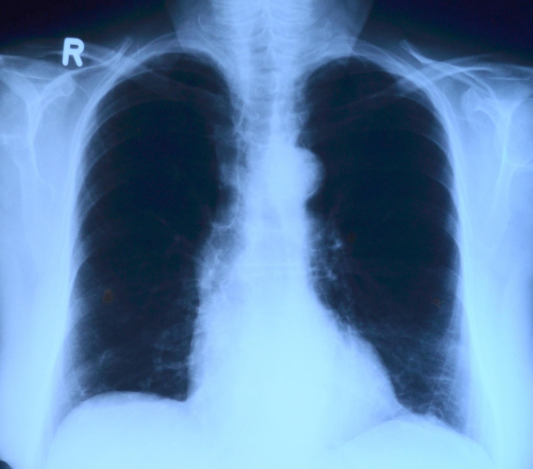

폐렴의 증상은 원인균과 환자의 연령, 기저질환 여부에 따라 다양하게 나타납니다. 가장 흔한 증상은 기침과 가래이며, 고열과 오한, 흉통이 동반되는 경우가 많습니다. 기침 시 누런색 또는 녹색 가래가 나오거나, 심한 경우 피가 섞여 나올 수도 있습니다. 호흡기 증상 외에도 전신 증상이 함께 나타나는 것이 폐렴의 특징입니다. 전신 쇠약감, 식욕 저하, 두통, 근육통이 지속되며, 고령자의 경우 발열 없이 의식 저하나 혼돈 상태로 나타나는 경우도 있어 조기 발견이 어렵습니다. 증상이 진행되면 숨이 차고 호흡이 빨라지며, 산소포화도가 떨어지는 저산소증이 발생할 수 있습니다. 이는 입원 치료가 필요한 중증 폐렴의 신호로 판단됩니다. 폐렴의 정확한 진단을 위해 병원에서는 여러 검사를 종합적으로 시행합니다. 가장 기본적인 검사는 흉부 X-ray 촬영으로, 폐에 염증 음영이 있는지를 확인합니다. 필요에 따라 흉부 CT를 통해 병변의 범위와 중증도를 보다 정밀하게 평가합니다. 혈액검사는 염증 수치와 백혈구 수치를 확인하여 감염 여부를 판단하는 데 활용됩니다. C-반응성 단백질(CRP)이나 프로칼시토닌 수치는 폐렴의 활성도를 평가하는 지표로 사용됩니다. 가래 배양 검사는 원인균을 정확히 확인하여 적절한 항생제를 선택하는 데 중요한 역할을 합니다. 최근에는 신속 항원 검사나 분자진단 기법을 통해 바이러스성 폐렴 여부를 빠르게 확인하는 경우도 증가하고 있습니다.